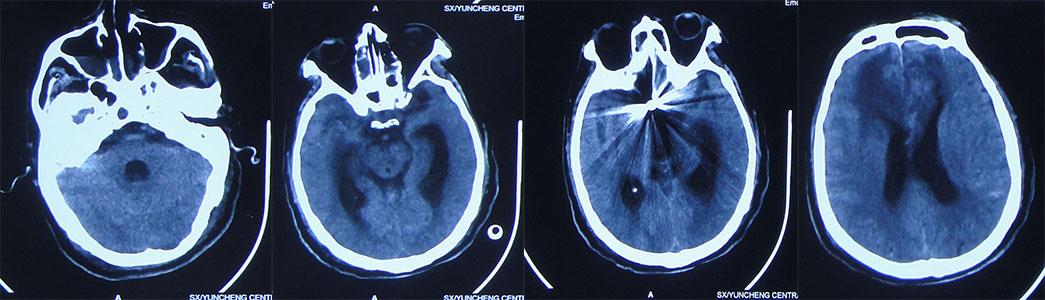

入院当天查头部CT示脑积水,前交通动脉瘤栓塞术后的金属影( 图-12 )。

图-12: 2020年11月13日头部CT

入院后完善检查,于2020年11月14日,脑室外引流术,流出黄色脑脊液。术后当天复查头部CT( 图-13 )脑室明显缩小,引流管位置满意。

图-13: 2020年11月14头部CT

2020年11月30日(入院17天,术后16天)脑脊液多次培养无细菌生长,行脑室长程引流术,术前复查头部CT( 图-16 ),脑室周围水肿变淡,正常脑室。

图-16: 2020年11月30头CT